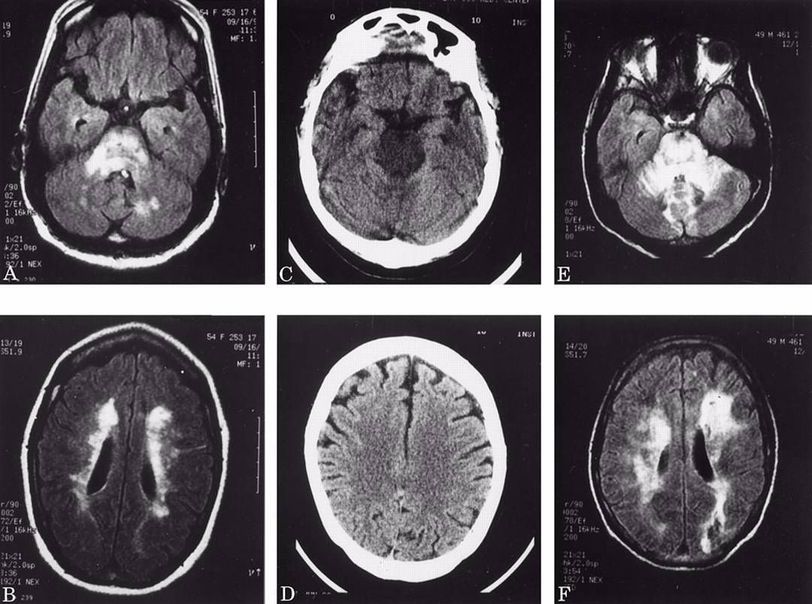

Hypertensive Encephalopathy is a condition that arises from rapid rise in the blood pressure that overwhelms the autoregulatory mechanisms in the brain leading to blood-brain barrier permeability and brain edema. Symptoms are headache, fits, speech and vision disturbances, and signs of papilloedema. Figure (A,B,E,and F) MRI of two different patinets shows signal changes in brain stem and cerebellum. (C, and D) CT scan of another patient shows mild swelling in pontine tegmentum. Diagnosis is by exclusion. The neurological symptoms are usually reversible if the blood pressure is controlled.